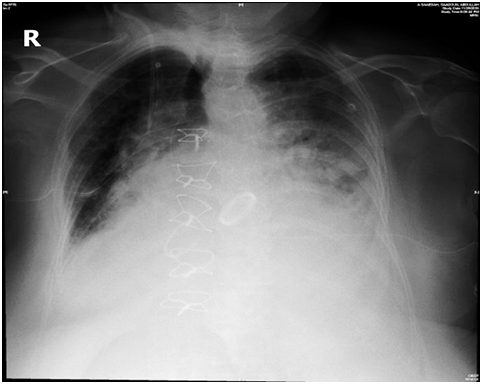

57- year-old women underwent 2 vessel coronary artery bypass grafting (CABG), Mechanical mitral valve replacement and tricuspid valve repair. She required a chest drain insertion for worsening left sided pleural effusion this was done in the surgical intensive care unit using a 12 F pig tail. Shortly following the insertion she started to become breathless and hemodynamically compromised with a drop of her blood pressure and oxygen saturation. It was noted that the chest drain was draining frank blood which was clamped. Chest x-ray revealed an abnormal position of the drain across the heart (Figure 1). Bed side echocardiogram showed the drain traversing the left ventricle (Figure 2). Bubble study through the chest drain showed contrast bubbles inside the left ventricle confirming position of the drain and perforation of the left ventricle (Figure 3). The drain was kept in situ. She was taken to the operating theatre for an emergency left thoracotomy. It appeared that the drain was penetrating the left lung and the left ventricle (Figure 4).

Figure 1 Chest X- ray showing the chest tube crossing the heart.